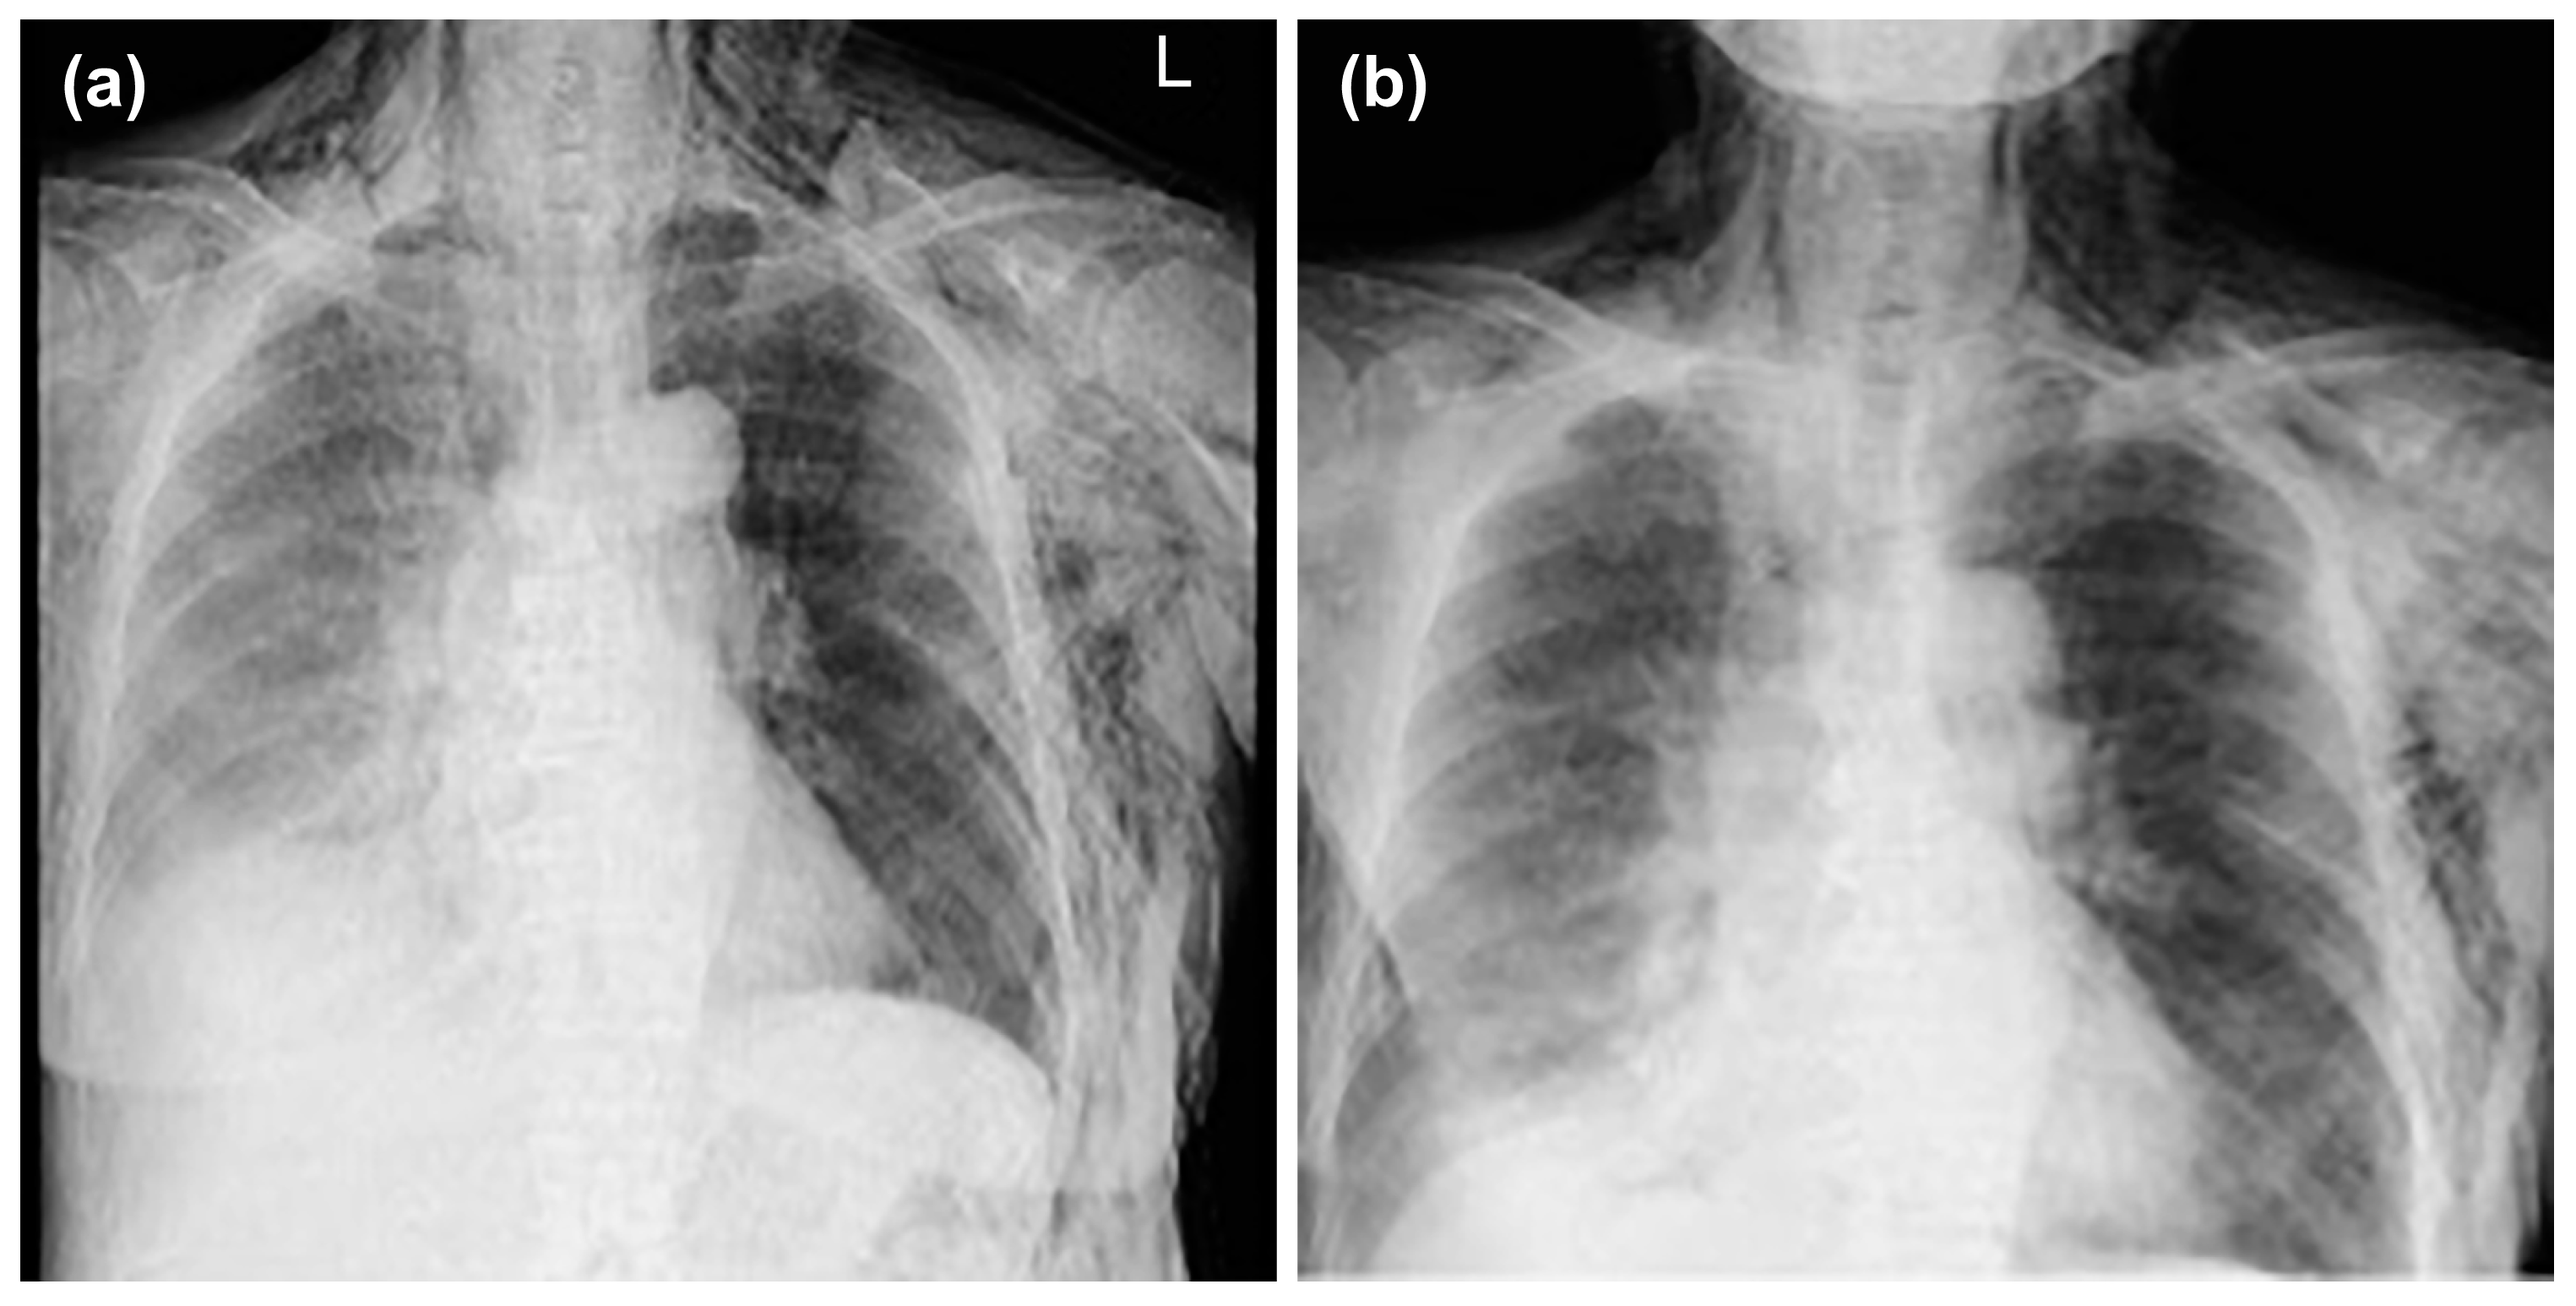

After insertion of the thoracic drain, a chest CT was performed; the scan showed mediastinal emphysema in the anterior mediastinum, with predominant subcutaneous emphysema in the left chest (Figure 3a,b).

Figure 3.

Mediastinal emphysema was observed in the anterior mediastinum, and subcutaneous emphysema was predominant on the left side of the chest (a). A drain was inserted between the lobes in the left thoracic cavity (b).